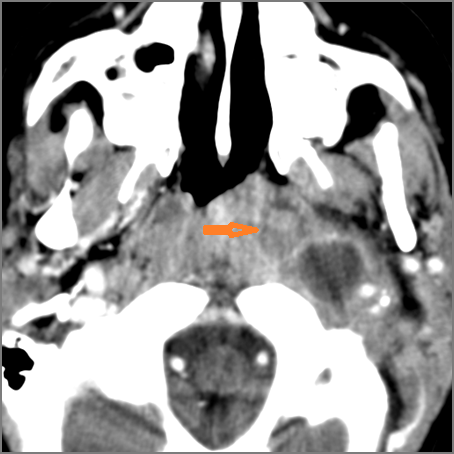

Retropharyngeal Lymph Nodes

If there is suppurative retropharyngeal adenopathy what is the maximum short axis dimension of the largest suppurative node. MEASUREMENT